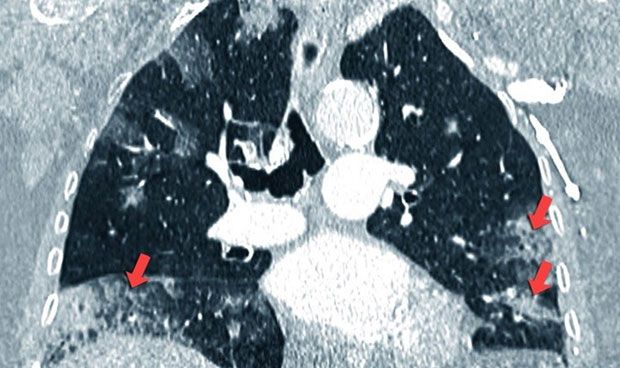

Investigadores de la Universidad de Kitasato (Japón) han identificado que los niveles de la proteína 4 asociadada al citoesqueleto (CKAP4) en la sangre de pacientes con cáncer de pulmón son significativamente más altos en pacientes con esta patología que en individuos sanos.

En un estudio publicado en la revista American Journal of Pathology, los investigadores han determinado que los niveles de CKAP4 ya están elevados en la sangre de pacientes con enfermedad en estadio I, convirtiéndolo en un posible biomarcador no invasivo que podría cambiar las prácticas actuales en el diagnóstico y tratamiento de algunos tipos de cáncer de pulmón, incluyendo aquellos que no son de células pequeñas.